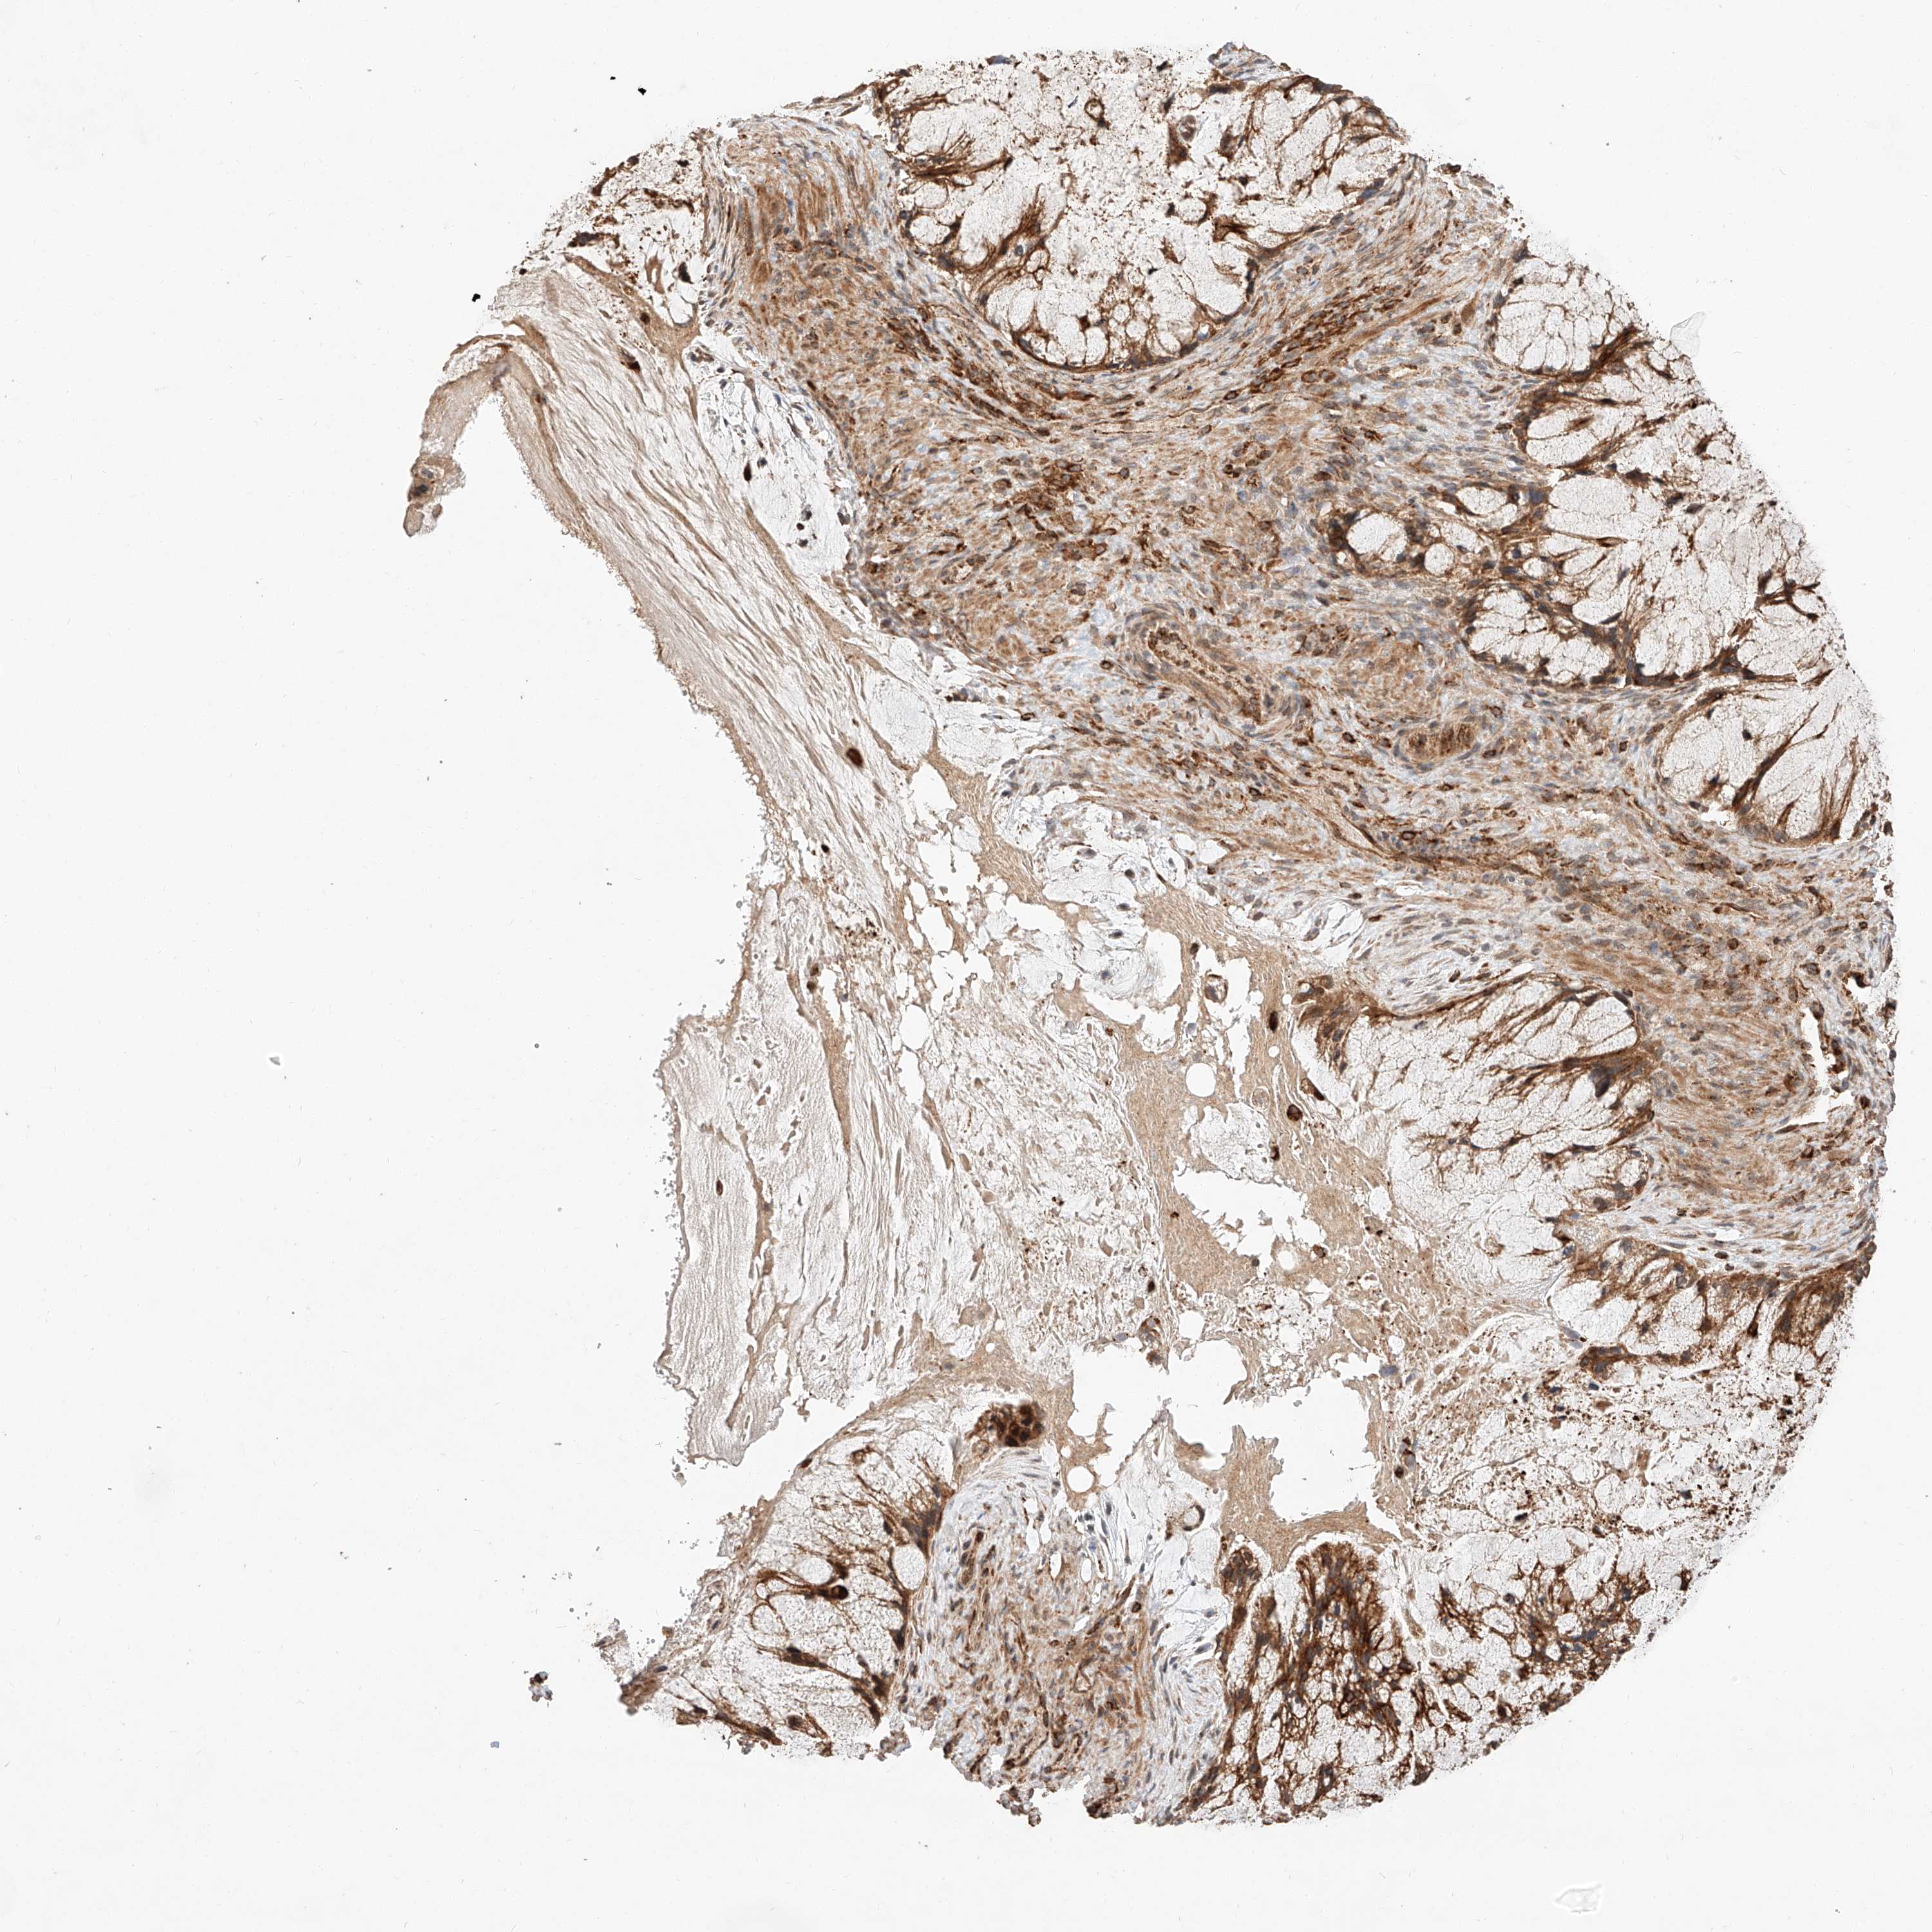

OVARIAN CANCER - Protein expressioni

A mouse-over function shows sample information and annotation data. Click on an image to view it in a full screen mode. Samples can be filtered based on level of antibody staining by selecting one or several of the following categories: high, medium, low and not detected. The assay and annotation is described here.

Note that samples used for immunohistochemistry by the Human Protein Atlas do not correspond to samples in the TCGA dataset.

Antibody stainingi

Antibody staining in the annotated cell types in the current human tissue is reported as not detected, low, medium, or high, based on conventional immunohistochemistry profiling in selected tissues. This score is based on the combination of the staining intensity and fraction of stained cells.

Each image is clickable and will lead to virtual microscopy that enables deeper exploration of all samples and also displays staining intensity scores, fraction scores and subcellular localization as well as patient and tissue information for each sample.

Antibody HPA028860

Staining

High

Medium

Low

Not detected

Intensity

Strong

Moderate

Weak

Negative

Quantity

>75%

75%-25%

<25%

None

Location

Nuclear

Cytoplasmic/membranous

Cytoplasmic/membranous,nuclear

Cystadenocarcinoma, serous, NOS

Carcinoma, endometroid

Cystadenocarcinoma, mucinous, NOS

Carcinoma, NOS